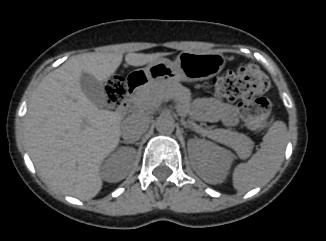

Мультиспиральная компьютерная томография желчного пузыря применяется для оценки состояния стенок желчного пузыря, изучения содержимого его полости, выявления воспалительных изменений, конкрементов и опухолевых новообразований.

В клинике «Доступная медицина» исследование проводится на новейшем 128-срезовом томографе TOSHIBA AQUILION CXL, который позволяет проводить исследование за короткий промежуток времени при сниженной лучевой нагрузке. Посредством инновационных компьютерных программ томограф преобразует полученные данные в 3D-изображения желчного пузыря и желчевыводящих протоков. Это помогает диагностировать заболевания гепатобилиарной системы особенно при нетипичной клинической картине, когда при помощи других методов обследования (УЗИ, МРТ) не удается выявить причину нарушения оттока желчи из желчного пузыря.

МСКТ желчного пузыря в большинстве случаев проводится с применением контрастирования. Пациенту внутривенно вводится рентгеноконтрастное вещество на основе йода. Препарат с током крови попадает в исследуемую область и усиливает контрастность патологических участков, что делает их видимыми на фоне здоровых тканей. При подозрениях на онкологический процесс метод компьютерной томографии с контрастированием помогает обнаружить патологию на раннем этапе развития и провести своевременное лечение.

Что покажет КТ желчного пузыря

- камни желчного пузыря и его протоков;

- холангит и холецистит;

- абсцессы;

- нарушения кровоснабжения, травмы, кровоизлияния;

- воспалительные процессы в желчном пузыре и поджелудочной железе.